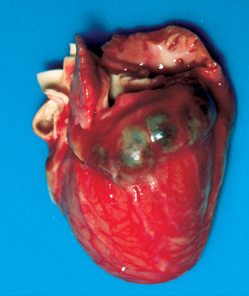

infant heart. (cardiac amyloidosis/endocardial fibroelastosis/hypoplastic left heart syndrome)

endocardial fibroelastosis (fibroelastotic thickening of the endocardium of the left ventricle, may also affect valves)